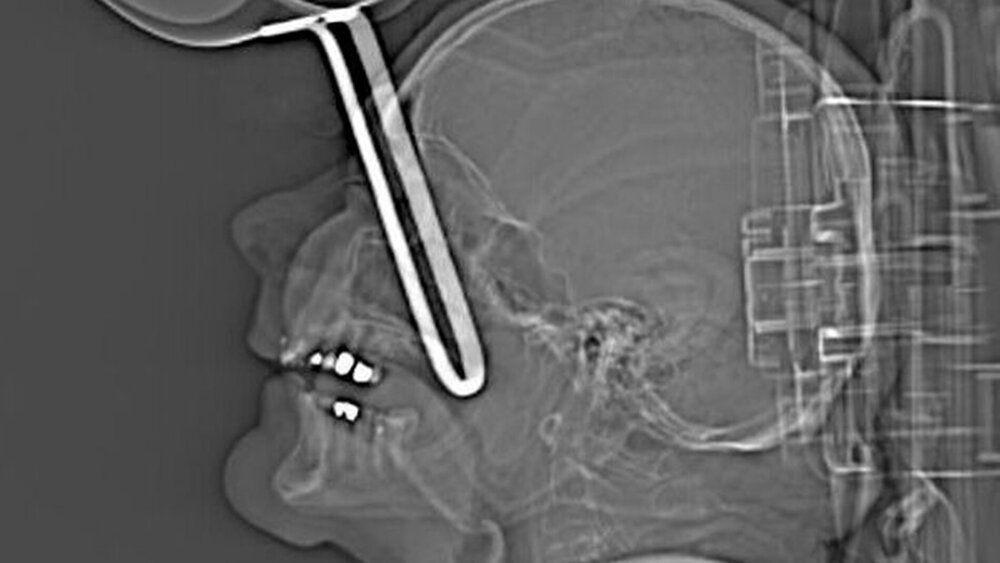

Durch den Zusammenstoß wurde ihr Unterkiefer gespalten und die gesamte linke untere Gesichtshälfte bis zum Gelenk verschoben. Dabei rissen nach Auskunft ihres Arztes Dr. Ricardo Mohammed-Ali, Facharzt für Gesichtsrekonstruktion, auch der Nervus mentalis und ein weiterer Seitenarm des Nervus alveolaris inferior. Bei Einlieferung in das Kinderkrankenhaus Sheffield des Nationalen Gesundheitsdienstes (NHS) wurde der beschädigte Gesichtsteil nur noch von einem etwa ein Zentimeter breiten Hautstreifen gehalten.

Emily wurde mit einem Rettungswagen in die Notaufnahme nach Sheffield gebracht. Nach der Untersuchung wurde sie sofort operiert. Die Operation dauerte nach Auskunft des Krankenhauses fast fünf Stunden. Insgesamt drei Titanplatten wurden in den Kiefer gesetzt, ein Knochen entfernt und abschließend die Wunde mit 160 Nadelstichen genäht. Bis auf einen Zahn konnten alle Zähne erhalten werden.